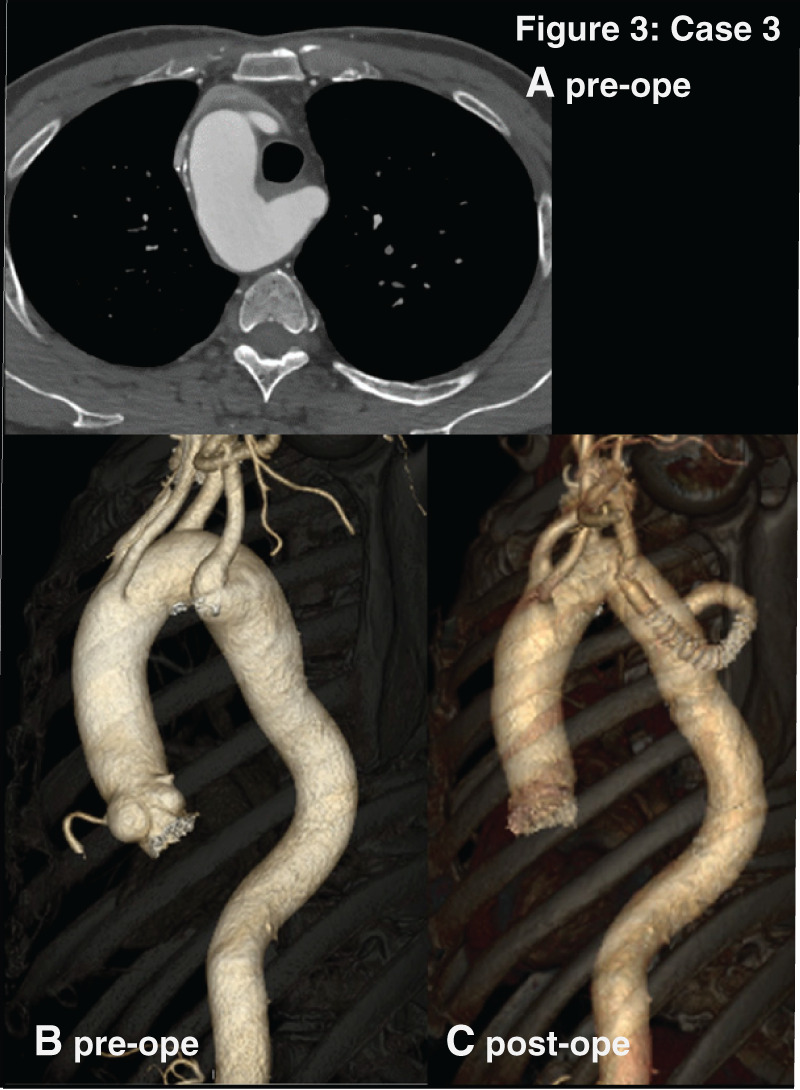

Case presentation: Four patients with right-sided aortic arch underwent different surgeries for Kommerell's diverticulum. The pattern of aortic arch was a mirror-image of the normal left aortic arch in Cases 1 and 2. In Cases 3 and 4, it was right-sided aortic arch with an aberrant left subclavian artery as its last branch. Cases 1 and 3 presented with compression symptoms caused by Kommerell's diverticulum. They underwent open surgery or thoracic endovascular aortic repair through the different approaches. Their postoperative courses were favorable.